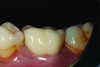

(5.) Delivery of a 3Y monolithic zirconia crown on tooth No. 19 with a resin-modified glass-ionomer cement.

Figure 5

(6.) Posttreatment retracted close-up view of the restored tooth No. 19 (Case provided by class of 2024 dental student Forrest Fontenot, University of Alabama at Birmingham School of Dentistry.).

Figure 6

Therefore, for crown preparations with "ideal" retention and resistance form, it is questionable whether bonding provides any further benefit. Moreover, bonding could be detrimental to the clinical outcome. In a scenario involving a well bonded 3Y or perhaps even 4Y monolithic zirconia crown of adequate thickness, given that the restoration is not likely to break or debond, the only other logical complications that may arise are biologic issues with the underlying tooth. Thus, a prudent clinician placing a highly fracture resistant zirconia crown on an ideal preparation would preferably deliver the restoration with a resin-modified glass-ionomer cement after it had been air abraded and treated with a zirconia primer (Figure 4 through Figure 6).